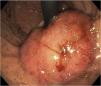

Presentamos el caso de un paciente varón de 15 años, que acude a consulta externa del Hospital Central del Estado de Chihuahua con historia de 4 meses de disfagia progresiva, síndrome anémico y pérdida de peso. Se envía a hospitalización, documentando Hb de 5.5g/dl con VCM de 74fl, HCM de 24pg y plaquetas de 500×103μl. Se transfunden 2 paquetes globulares, y se pasa a endoscopia superior, encontrando durante la retroflexión una tumoración en cardias de 6cm con mucosa de aspecto adenomatoso, friable, con sangrado durante la insuflación, se extiende hacia curvatura menor y tercio inferior de esófago, obstruyendo parcialmente la luz (fig. 1), correspondiendo a un EGJA tipo II según Siewert. La tomografía toracoabdominal mostró una tumoración gástrica de 5.7×2.6cm de aspecto infiltrativo con invasión a ganglios perigástricos, dando una clasificación cTNM de T3, N2, M0 (fig. 2). Los hallazgos de histopatología con inmunohistoquímica reportaron un adenocarcinoma moderadamente diferenciado con invasión del estroma, sin inestabilidad microsatelital, expresión integral de proteínas reparadoras del ADN y nula expresión de p53. Se administró quimioterapia preoperatoria con fluorouracilo con leucovorina, oxaliplatino y docetaxel (FLOT), hace 4 meses se realizó gastrectomía total ampliada con resección transhiatal de esófago con reconstrucción con Y de Roux retromesocólica, posterior a la cirugía se dieron 4 ciclos más de quimioterapia con esquema FLOT y actualmente en tratamiento con radioterapia con adecuada respuesta.